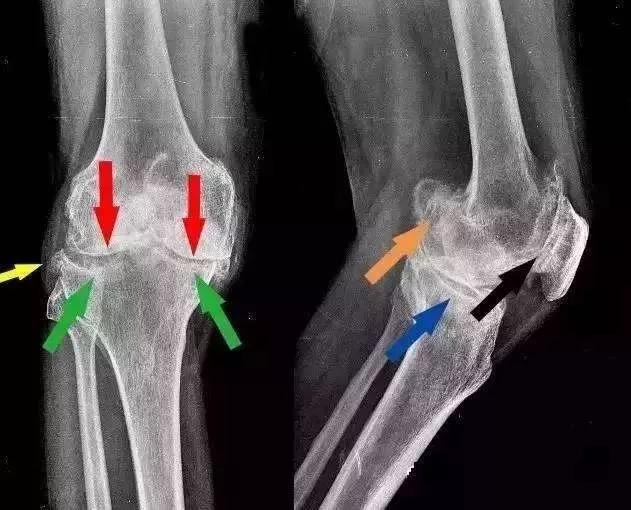

此时人体还面临一个严峻的情况——骨质增生。

骨质增生是人体衰老的正常退化现象,一般不会引起症状。只有增生的骨刺伤到周围组织后才会出现不适。

膝关节长期承受较大压力,软骨磨损严重,增生的骨刺很容易深入到周围组织,引发一系列病变。

随着病情发展,出现关节积液、关节囊肿胀。